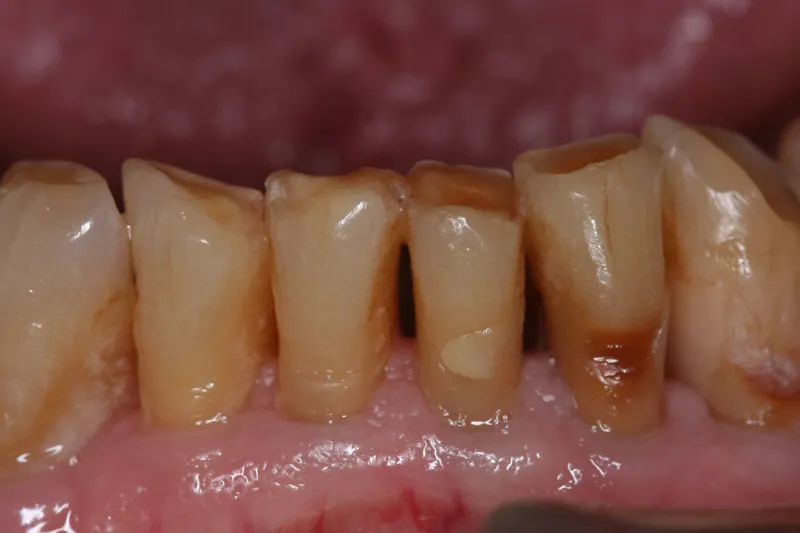

Management of root caries is the biggest challenge in the dental treatment of older patients. A management strategy should be based on good oral hygiene and effective preventive measures. Resin modified glass ionomer cements, (GICs), are usually the best restorative materials due to their good bonding ability to the dentine structure. Older patients’ healing responses to endodontic and periodontal therapies do not differ from those of younger adults. However, in difficult to treat cases, dental extraction is often the best way to eliminate periapical and periodontal infections. The primary treatment goal should always be elimination of oral pain and infections and the establishment good oral health.

This article aims to provide a comprehensive overview of the unique aspects of dental diseases among older people, emphasizing the occurrence of root caries and periodontal diseases, which are the main dental diseases that typically involve a large number of dentate older people. It also attempts to describe management strategies and highlights minimally invasive treatment concepts for older people.